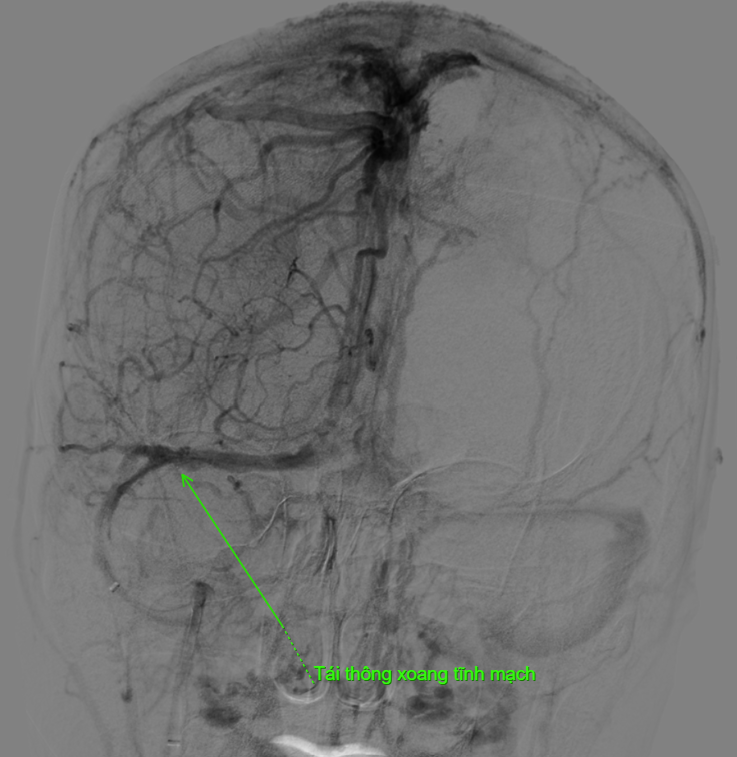

“Không giống như huyết khối động mạch, để lấy huyết khối tĩnh mạch não chúng tôi phải tiếp cận qua đường tĩnh mạch. Trước tiên, ê-kíp tiến hành chụp động mạch não để hiện hình hệ thống xoang tĩnh mạch và xác định vị trí huyết khối trên máy DSA. Sau đó, hệ thống dụng cụ được đưa từ tĩnh mạch đùi lên tĩnh mạch cảnh trong phải để lấy huyết khối từ tĩnh mạch cảnh trong lên đến xoang dọc trên - vị trí có huyết khối. Từ đây, chúng tôi lấy toàn bộ huyết khối từ xoang dọc trên xuống tĩnh mạch cảnh trong để tái thông hệ thống xoang tĩnh mạch não. Ca can thiệp kéo dài hơn 2 giờ đồng hồ. Ngay sau thủ thuật, dòng chảy trong hệ thống xoang tĩnh mạch được cải thiện rõ rệt, bệnh nhân giảm nhanh triệu chứng đau đầu và tránh được nguy cơ xuất huyết não, biến chứng nguy hiểm có thể xảy ra nếu xoang tĩnh mạch không được tái thông kịp thời”, bác sĩ Hải thông tin thêm.

Sự kết hợp giữa can thiệp hút huyết khối và điều trị nội khoa đã giúp tái thông hiệu quả dòng chảy tĩnh mạch, đồng thời ngăn ngừa nguy cơ hình thành huyết khối mới. Kỹ thuật này không phải là chỉ định thường quy vì độ phức tạp cao và chỉ áp dụng trong các trường hợp đặc biệt: Tắc nhiều tĩnh mạch lớn; Điều trị nội khoa không đáp ứng; Triệu chứng tiến triển nặng.

Sau 5 ngày can thiệp, bệnh nhân đã hoàn toàn hết triệu chứng đau đầu, thể trạng ổn định và đáp ứng điều trị tốt. Các chỉ số cận lâm sàng được cải thiện rõ rệt, bệnh nhân tỉnh táo, giao tiếp tốt và sinh hoạt gần như bình thường. Hiện tại, bệnh nhân tiếp tục được theo dõi và phục hồi chức năng nhằm phòng ngừa nguy cơ tái phát. Với tiến triển rất khả quan này, T. có thể sớm quay trở lại giảng đường đại học, tiếp tục học tập và sinh hoạt như trước đây, đồng thời sẽ được các bác sĩ hướng dẫn tái khám định kỳ để đảm bảo quá trình hồi phục lâu dài và bền vững.